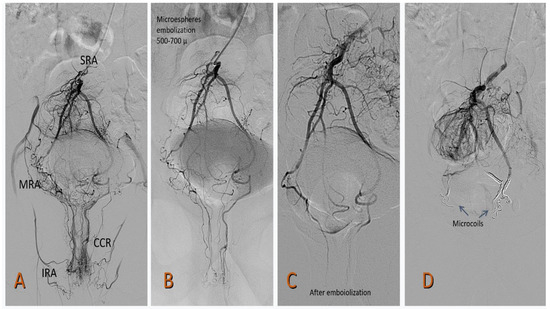

Using a 0.035-inch, 150 cm hydrophilic guidewire (Radiofocus, Terumo, Tokyo, Japan) and a 5F, 125 cm MPA catheter (Cook Medical, Indiana, USA), the abdominal aorta was advanced, and the proximal segments of the inferior mesenteric artery and the superior rectal artery (SRA) were selected. A selective angiography of the SRA was performed by administering 12 mL and 4 mL/s of iodinated contrast (Optiray 320 Guerbet BP 57400) to determine the anatomy of the SRA and possible communication with the middle or inferior rectal artery. A 150 cm Progreat 2.4 or 2.7 Fr microcatheter (Radiofocus, Terumo, Tokyo, Japan) was placed as close as possible to the corpus cavernosum recti (Figure 1).

Figure 1.

Arteriography of the superior rectal artery (SRA) from the inferior mesenteric artery (IMA). (A) The highly developed right branch of the SRA that irrigates the corpus cavernosum rectum CCR is observed. From the origin of the SRA, a collateral arises that anastomoses with the middle rectal artery (MRA), a branch of the right internal iliac artery. The left branch of the SRA is underdeveloped. (B) Occlusion with Prestige coils of the right middle rectal artery (MRA) and the right superior rectal artery (SRA).

In all the cases, Prestige coils (Balt) with diameters of 2–5 mm and various lengths (10–40 cm) were used. Prestige microcoils were also used in re-embolization procedures in rebleeding patients and, if necessary, 500–700 µm Tris-acryl Gelatin microspheres (TAGM) (Merit Medical Spain) were used.

Figure 2.

A 49-year-old patient with grade II HD (Goligher) and French bleeding score (FBS) of 6: (A) Selective arteriography from the inferior mesenteric artery in which asymmetry of both superior rectal arteries is observed. The right SRA is highly developed with communication with the MRA and IRA. Both provide a lot of risk to the CCR. The left SRA is poorly developed. (B) Embolization with 500–700 µ microspheres (Merit Medical). (C). Acceptable result after embolization. (D) Distal embolization with Prestige microspheres (Balt medical). SRA: superior rectal artery, MRA: middle rectal artery, IRA: inferior rectal artery, CCR: corpus cavernosum rectum.